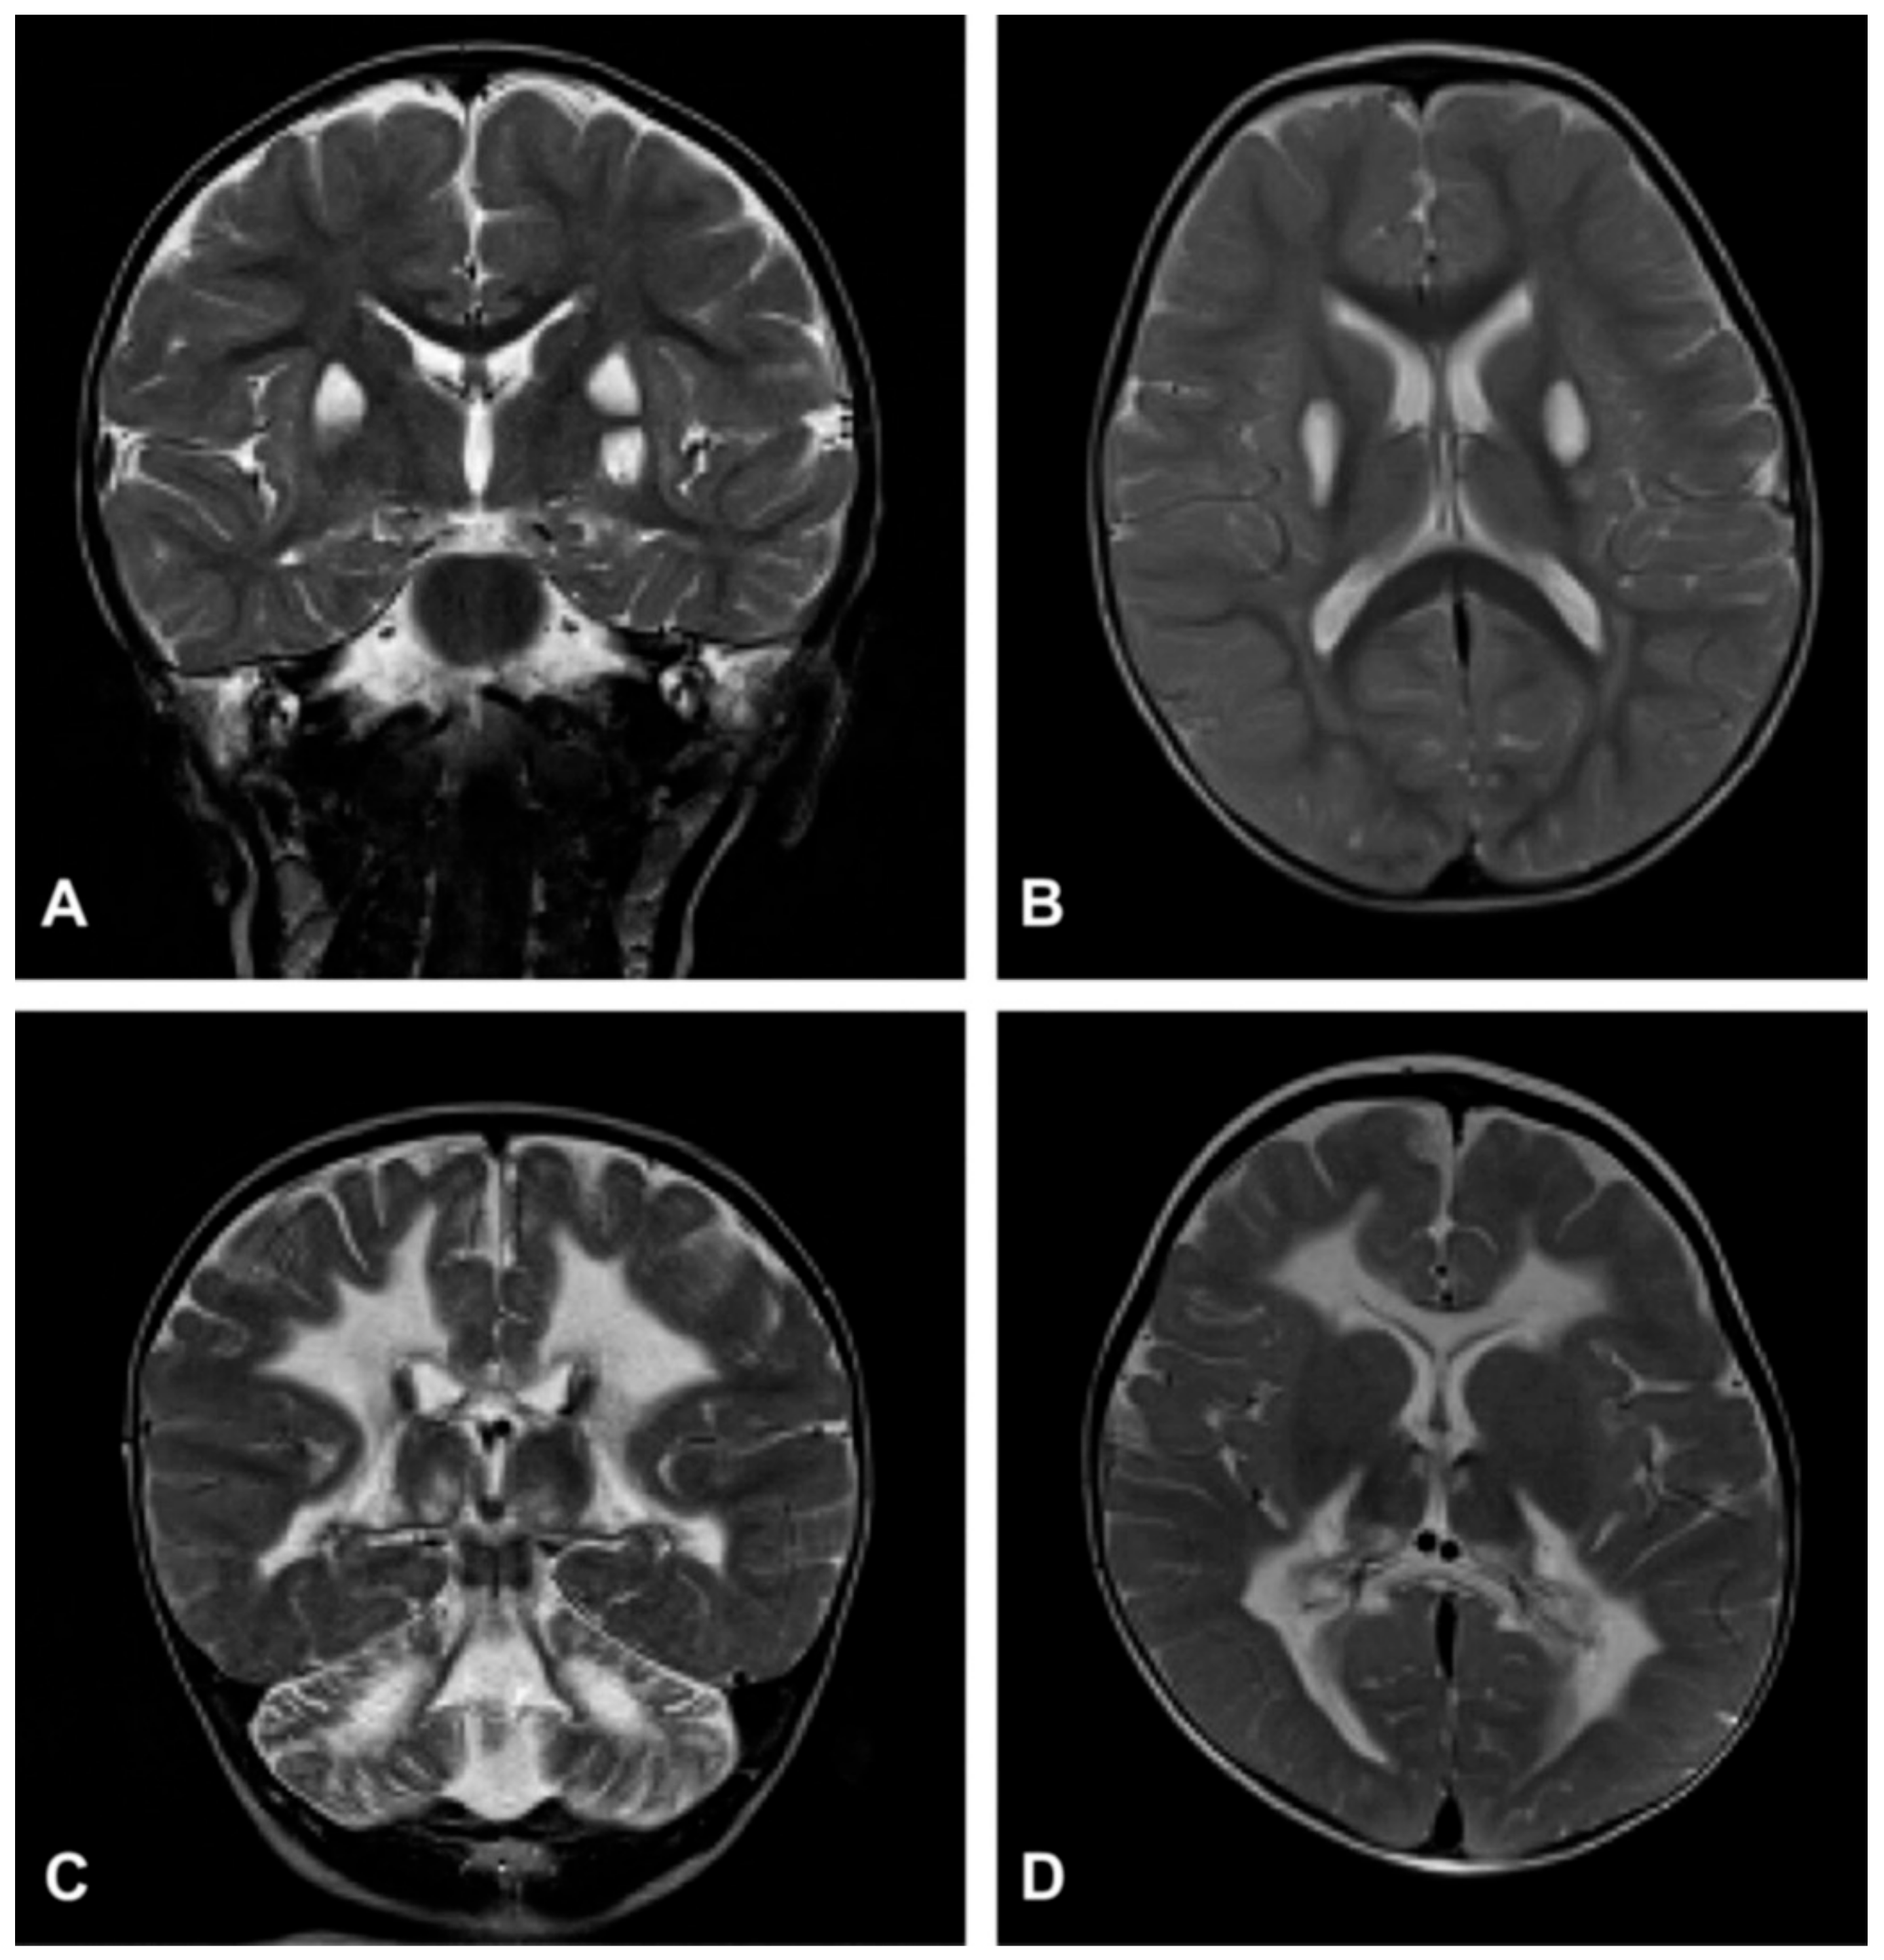

2.1. Necrotizing Encephalomyelopathy: Leigh Disease (LD)

Clinical Definition

- Barkovich, A.J.; Good, W.V.; Koch, T.K.; Berg, B.O. Mitochondrial Disorders: Analysis of Their Clinical and Imaging Characteristics. AJNR Am. J. Neuroradiol. 1993, 14, 1119–1137. [Google Scholar] [PubMed]